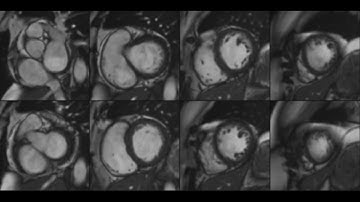

Local Motion Intensity Clustering LMIC Model for Segmentation of Right Ventricle in Cardiac MRI Imag